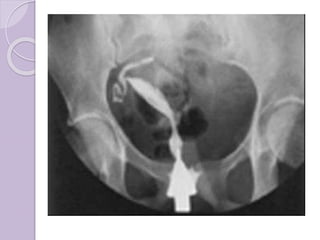

 Aparte del examen físico, se necesita

tomar imágenes para determinar las

características de la malformación:

Ultrasonografía ginecológica, resonancia

magnética pélvica o histerosalpingografía.

Un histerosalpingograma no es

considerado de utilidad debido a su

inhabilidad para evaluar el contorno

exterior del útero y distinguir entre un

bicornio y un útero particionado.

Adicionalmente una laparoscopia y/o

histeroscopia pueden ser recetados.